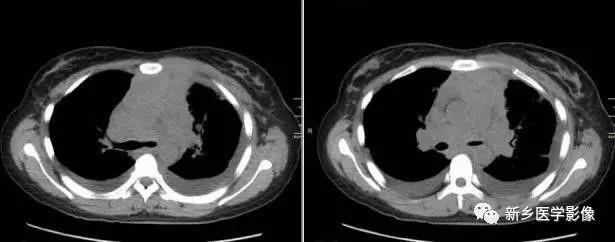

胸内结节性甲状腺肿CT图像

a. CTCT平扫示上纵隔气管两侧甲状腺软组织密度肿块,密度欠均匀,气管受压移位、变形 b. 增强后明显不均匀强化